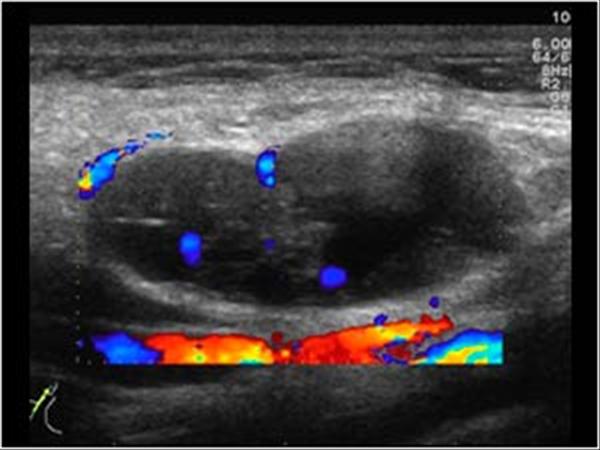

U tuyến nước bọt

» Thông tin: Nam giới – 64 tuổi.

» Lâm sàng: Khối vùng mang tai.

# U lympho tuyến nang (U Warthin) tuyến nước bọt mang tai.